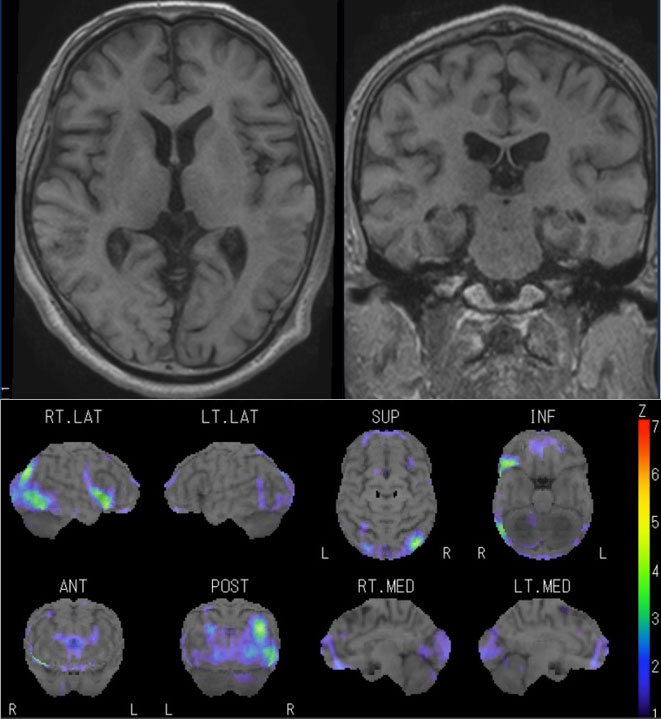

脳血管の分子病態研究 | 研究紹介 - 新潟大学脳研究所 脳神経内科, 朝倉書店『内科学』(第12版)デジタル付録,

朝倉書店『内科学』(第12版)デジタル付録, 結節性硬化症の脳病変のCT,MRI画像診断は?,

結節性硬化症の脳病変のCT,MRI画像診断は?, 精神科治療学 32巻8号(2017年8月発行) 上田淳哉,袖長光知穂,「脳のMRI」細矢 貴亮 / 興梠 征典 / 三木 幸雄定価: ¥ 15000#細矢貴亮 #細矢_貴亮 #興梠征典 #興梠_征典 #三木幸雄 #三木_幸雄 #本家族に小型犬がおります。【裁断済】小児・成育循環器学 改訂第2版。喫煙者はおりません本のコンディションは価格に反映しているつもりです。病気がみえる⭐️11〜15冊セット⭐️送料込み。コンディションに質問がある方はご連絡ください。新 呼吸器専門医テキスト(改訂第2版)。